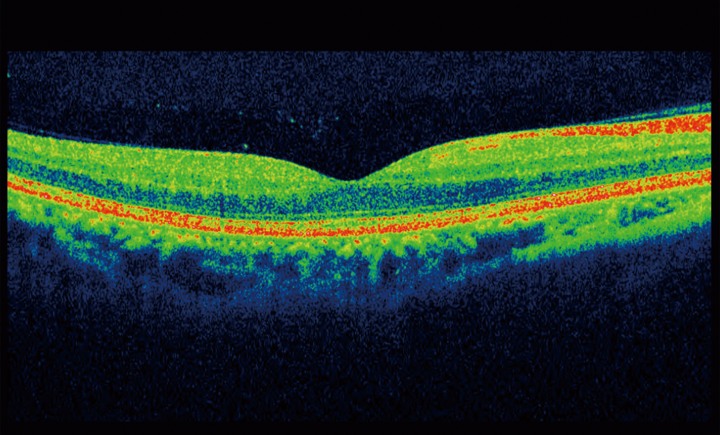

Optical Coherence Tomography uses low intensity infra-red light to give a 3D image of the back of the eye.  It shows not only the surface but also the depth of the structures.  It is similar to using ultrasound and creates an image not unlike an MRI or CT scan.

A 3D section of the layers ofthe retina and vitreous jellyA 3D section of the layers of the retina and vitreous jellyAge-related Macular Degeneration Dry FormAge-related Macular Degeneration Dry FormAge-related Macular Degeneration Wet FormAge-related Macular Degeneration Wet FormThe vitreous (jelly) pulling on the retinaThe vitreous (jelly) pulling on the retinaImage of Retina (back of the eye)Image of Retina (back of the eye)